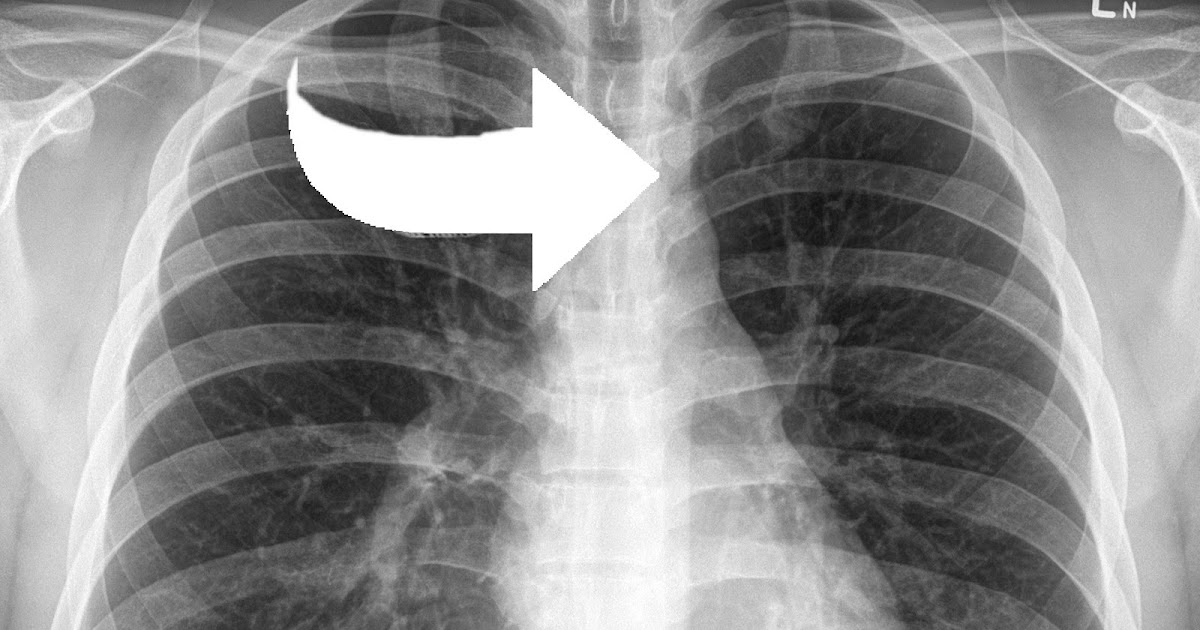

New AI tool can detect Covid infection from chest Xrays 98 accuracy Can A Chest X Ray Detect Costochondritis Costochondritis is an agonizing inflammation in the chest, often mistaken for a heart attack. The pain may be worse. Key sign is pain on. Check if you have costochondritis. md explores its origins, signs, diagnosis, and remedies. Costochondritis may cause sharp pain in the front or side of your chest. You or someone else has symptoms like: There is no. Can A Chest X Ray Detect Costochondritis.

New model can detect long COVID's effects using simple, 2D chest Xrays Can A Chest X Ray Detect Costochondritis You or someone else has symptoms like: Key sign is pain on. There is no laboratory or imaging test to confirm a diagnosis of costochondritis. Costochondritis may cause sharp pain in the front or side of your chest. Check if you have costochondritis. Costochondritis is an agonizing inflammation in the chest, often mistaken for a heart attack. But a health. Can A Chest X Ray Detect Costochondritis.